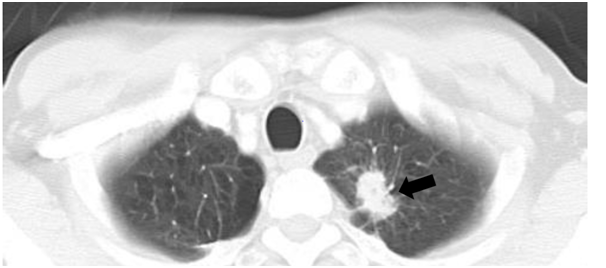

Preoperative sagittal magnetic resonance imaging (MRI) showed that the tumor was located in the dura mater at Th12 (Figure 2A–C). Compared with the spinal cord, the tumor had an iso-intensity signal in a T1-weighted MRI and high-intensity signal in a T2-weighted MRI (Figure 2A) (Figure 2B). The tumor was enhanced by Gadolinium with diethlenetriaminepentacetate (Gd-DTPA) (Figure 2C) (Figure 2D). The spinal nerve roots were compressed by the tumor, as observed on an enhanced T1-weighted axial image with Gd-DTPA (Figure 2D). The patient was diagnosed as having an intradural-extramedullary tumor and tumor resection surgery was performed to decompress the nerves.

Figure 2 Magnetic resonance image of the thoracic spine. A. T1-weighted sagittal imaging. B. T2-weighted sagittal imaging. C. Gadolinium with diethlenetriaminepentacetate (Gd-DTPA) enhanced sagittal imaging. D. Gd-DTPA enhanced axial imaging. An intradural-extramedullary tumor can be seen at the 12th thoracic vertebral body level. The tumor has an iso intensity in T1-weighted imaging (A) and high intensity in T2-weighted imaging (B) compared with the spinal cord (white arrow). The tumor was enhanced by Gd-DTPA (white arrow) (C, D).